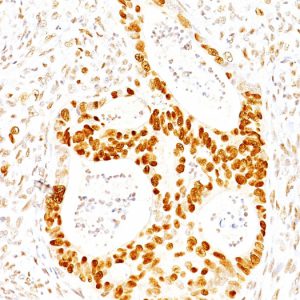

IHC analysis of formalin-fixed, paraffin-embedded human prostate. Strong nuclear staining using KIP1/1357 at 2ug/ml in PBS for 30min RT. HIER: Tris/EDTA, pH9.0, 45min. 2°C: HRP-polymer, 30min. DAB, 5min.